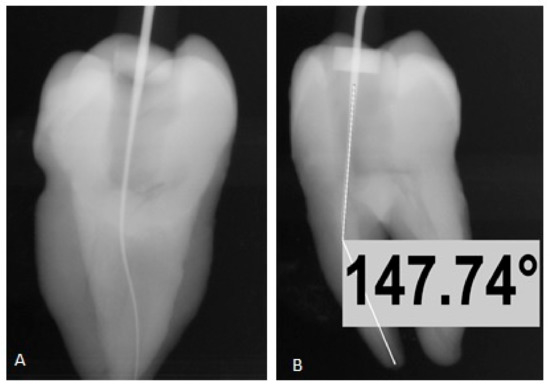

2.4. Determination of Canal Curvature Using Schneider Technique